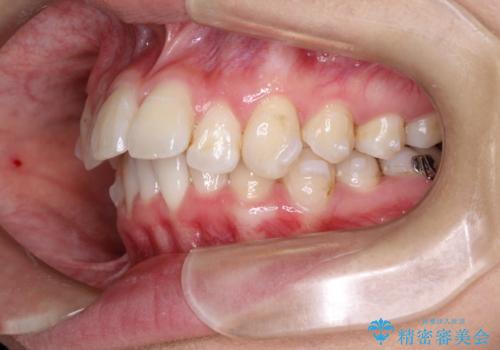

前歯の突出、深い噛み合わせ、ガタつきをマウスピース矯正(インビザライン)で治療した症例

- 初診時には上顎前歯の突出、前歯部の深いかみ合わせ、叢生が見られる状態でした。

このケースでは非抜歯にて奥歯を後方に移動させる事で前歯の突出を改善するスペースを作り出していますが、これはマウスピースと顎間ゴムの併用によるもので、患者様のご協力の賜物と言えます。

深い噛み合わせについてはシミュレーション上の結果と、予期される実際の歯の移動量とを考慮し、特殊なセットアップを行う事で望ましい結果を得ることができました。